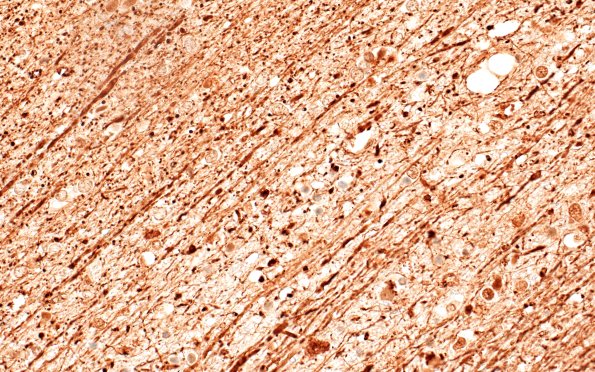

Several higher magnification images of the area between arrowheads in image 12D2 showing focal axon loss and swollen axonal spheroids at the margins of the embolic infarcts. Lucent empty vessels containing fat emboli are discernable close to individual infarcts. (NF IHC)